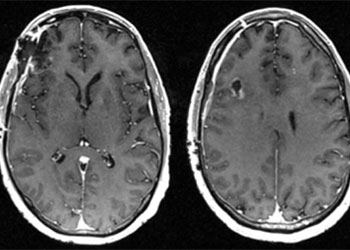

October 27, 2021Cerebral Metastases from Non-Small Cell Lung Cancer

October 27, 2021